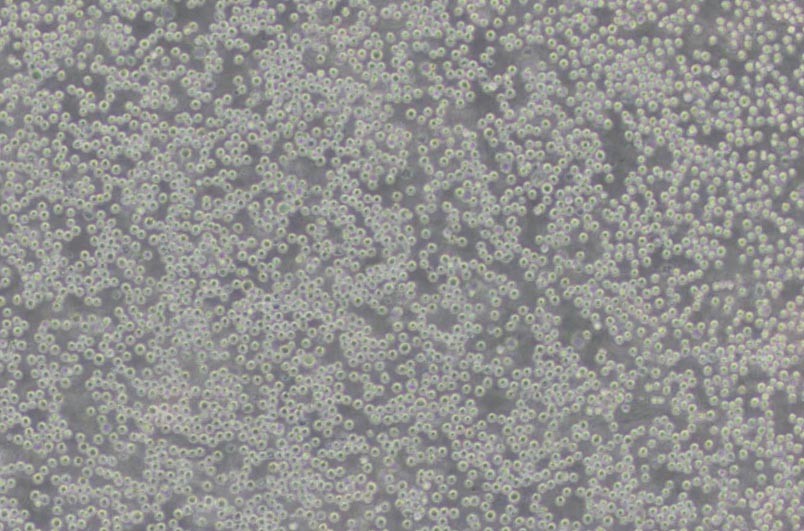

U-937人組織細(xì)胞淋巴瘤細(xì)胞

細(xì)胞形態(tài) : 單核細(xì)胞

生長(zhǎng)特性 : 懸浮細(xì)胞

U -937細(xì)胞是由Sundstrom 和Nilsson于1974年建立,取材于患組織細(xì)胞淋巴瘤病人的胸水。研究表明:U -937細(xì)胞能被人混合淋巴細(xì)胞培養(yǎng)上清,佛波脂、維生素D 3、γ干擾素、腫瘤壞死因子和維甲酸誘導(dǎo)終末單核細(xì)胞分化。U -937細(xì)胞免疫球蛋白產(chǎn)物和E B 病毒表達(dá)為陰性;U -937細(xì)胞表達(dá)Fas抗原且對(duì)T N F和抗-Fas抗體敏感。